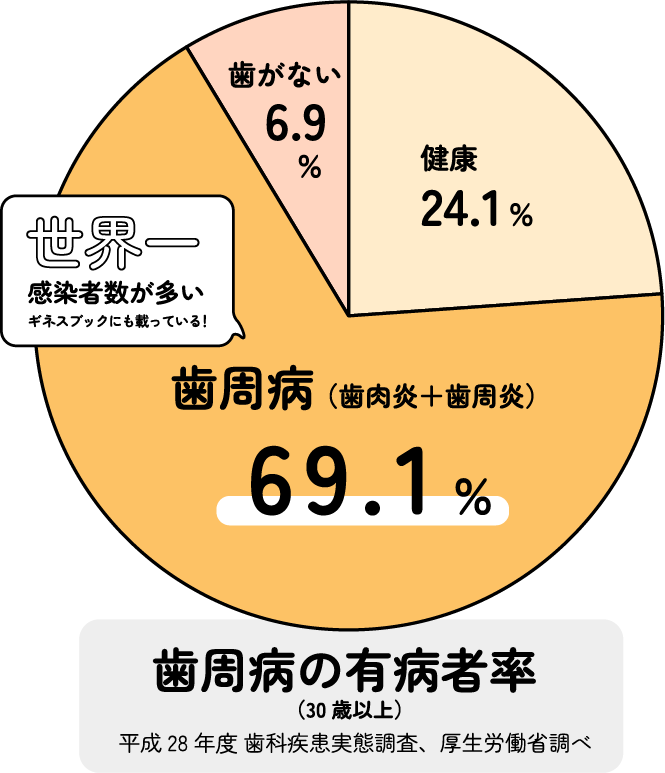

歯周病と聞くと、中高年以降の方がかかるんじゃない?と思われがちですが、なんと30代以上の10人中7人の方が罹患している誰もがかかりうる病気なんです。グラフは軽い歯肉炎程度の方も加わえた発生率です。